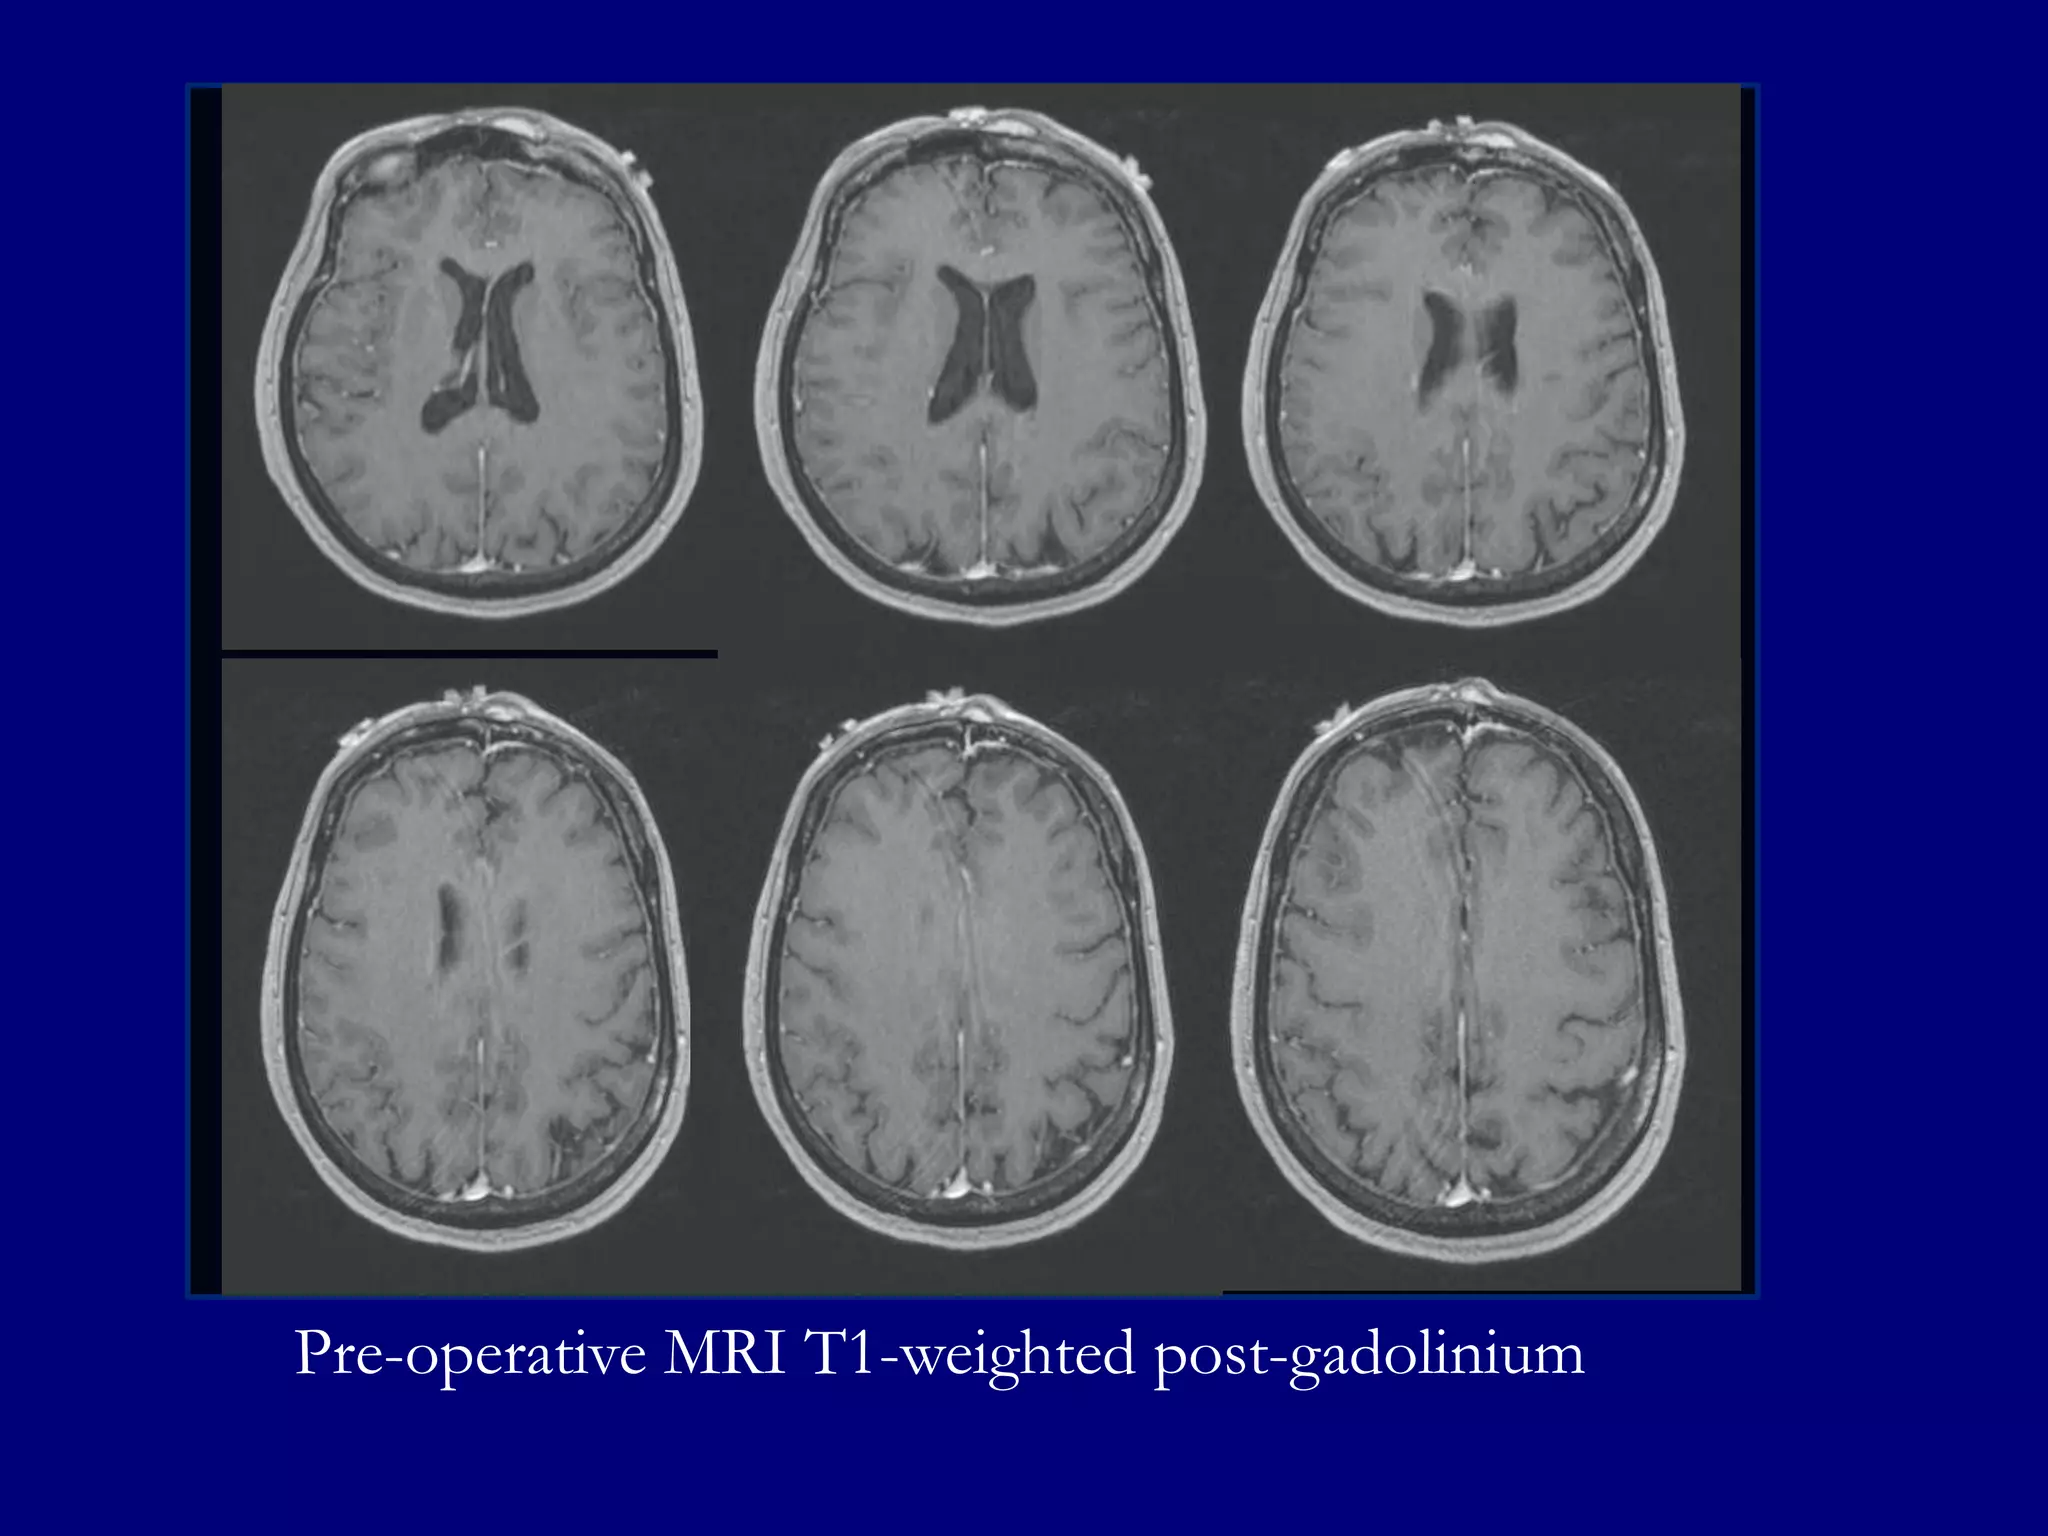

Pre-operative MRI T1-weighted post-gadolinium

Based on MR features,

surgery was cancelled and a

diagnostic Ultrasound was

performed